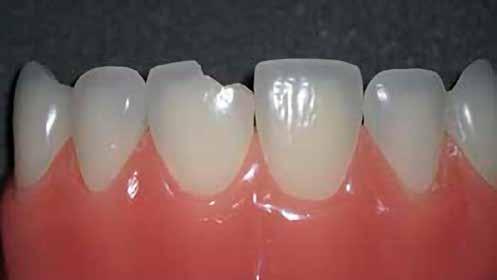

A cikkünkben bemutatásra kerülő eset ellátása során preparációt héjak készre vitele során a platinafólia technikát alkalmaztuk.

kívül vékonyak, és ezáltal a végleges rögzítésük előtt jelentős olyan minimál invazív kezelési eljárásnak számítanak, amely

elérni. A fent leírtak alapján bátran

preparációt nem igénylő héjak készítése mellett döntöttünk. A alkalmaztuk. Annak ellenére, hogy az elkészítésre kerülő héjak rendjelentős törésveszéllyel állunk szemben, összességében mégis amely segítségével kifogástalan esztétikai eredményeket lehet javasoljuk e módszer alkalmazását.